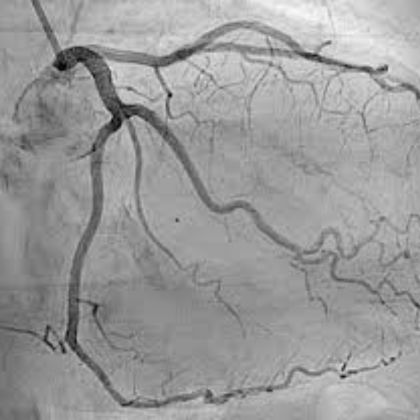

- Angiografia: Angiografia jest procedurą obrazowania wykorzystującą substancję kontrastową i promieniowanie rentgenowskie do wizualizacji tętnic. Jest często wykonywana w przypadkach podejrzenia zwężenia lub blokady tętnic.